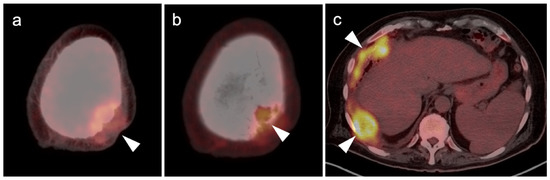

- Umemura, H.; Yamasaki, O.; Kaji, T.; Hamada, T.; Otsuka, M.; Asagoe, K.; Iwatsuki, K. Prognostic value of 18 F-fluorodeoxyglucose positron emission tomography/computed tomography in patients with cutaneous angiosarcoma: A retrospective study of 18 cases. J. Dermatol. 2017, 44, 1046–1049. [Google Scholar] [CrossRef] [Green Version]

- Tokmak, E.; Özkan, E.; Yağcı, S.; Kır, K.M. F18-FDG PET/CT Scanning in Angiosarcoma: Report of Two Cases. Mol. Imaging Radionucl. Ther. 2011, 20, 63–66. [Google Scholar] [CrossRef]